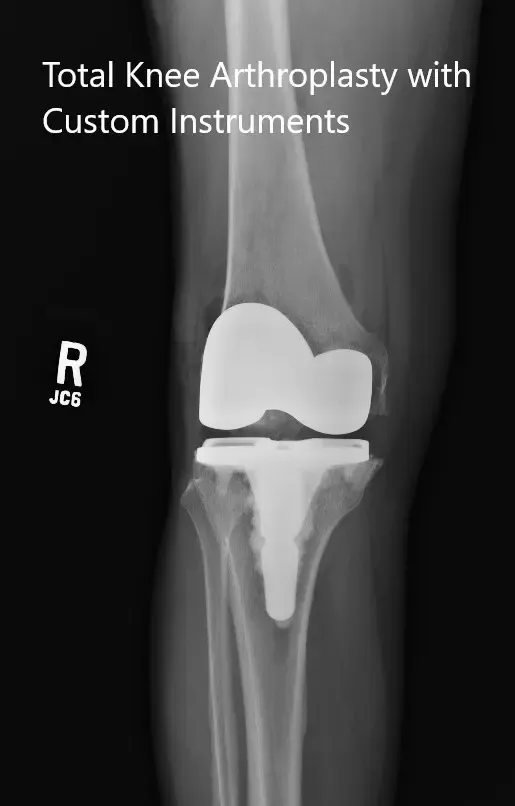

IMPLANTES UTILIZADOS: Fémur estabilizado posterior, talla 3, con una tibia Persona de 5 grados con tallo, tallo C, con inserto de polietileno estabilizado posterior de 10 mm con extensión del tallo de 14 mm de diámetro y rótula cementada de 29 m.

Radiografías postoperatorias que muestran las vistas anteroposterior y lateral de la rodilla derecha.